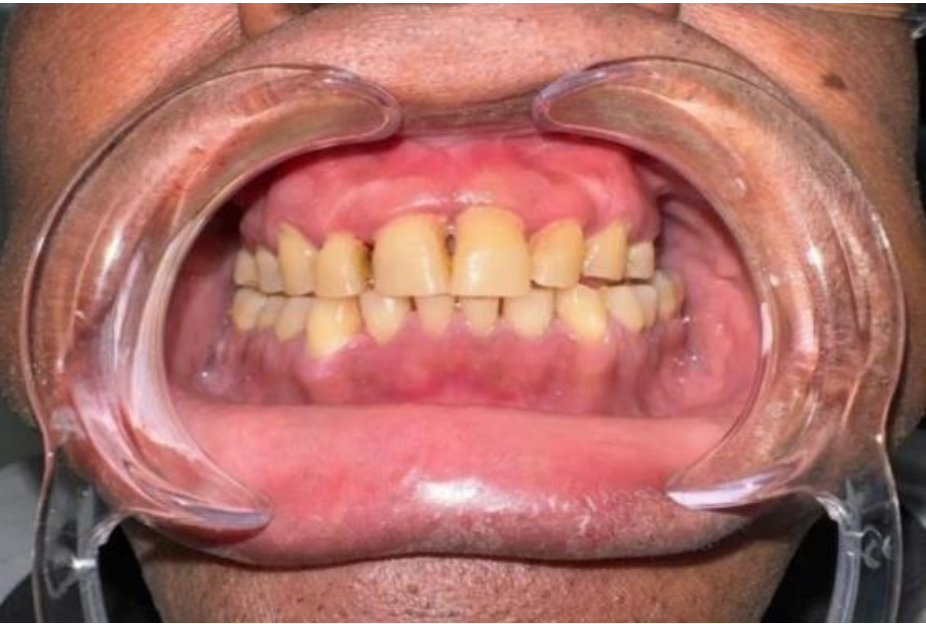

O presente estudo trata-se de um relato de caso clínico realizado na Clínica Odontológica da UNIFAMAZ, onde foi atendido um paciente do sexo masculino, 46 anos, diagnosticado com esquizofrenia. O paciente compareceu à clínica acompanhado de sua irmã, relatando incômodo estético relacionado à saúde bucal.

Durante o exame clínico intraoral, foram observadas raízes residuais nos elementos 17, 26 e 27, sinais de bruxismo, restaurações anteriores e presença de doença periodontal. O plano de tratamento foi estabelecido com foco na reabilitação funcional e estética, bem como na educação em saúde bucal, considerando de forma integrada as condições clínicas, emocionais e comportamentais do paciente. A responsável relatou que, em atendimentos odontológicos anteriores, o paciente havia interrompido o tratamento devido ao medo e à dificuldade de adaptação ao ambiente clínico. Diante desse histórico, estabeleceu-se que a realização de um processo de condicionamento prévio seria imprescindível antes da execução de procedimentos invasivos, com o intuito de favorecer o desenvolvimento de confiança, minimizar a ansiedade e proporcionar maior conforto ao longo das sessões. Dessa forma, optou-se pela realização dos procedimentos restauradores inicialmente, deixando a exodontia para uma etapa posterior, quando o paciente já apresentava melhor adaptação ao atendimento, garantindo um manejo mais seguro, humanizado e alinhado às suas necessidades. Antes do início do tratamento, o paciente e sua responsável legal assinaram o Termo de Consentimento Livre e Esclarecido (TCLE) e o Termo de Assentimento Livre e Esclarecido (TALE), autorizando a divulgação do caso para fins acadêmicos.

Figura 14. Arcada dental do paciente em seu retorno.